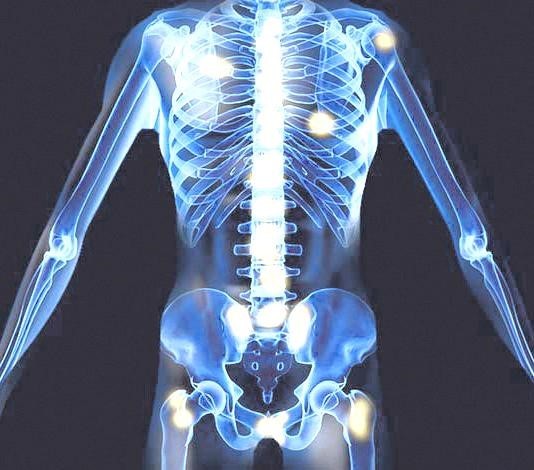

전립선암은 척수를 압박해서 하지 운동 장애를 일으킬 수 있으며, 이는 전체 전립선암 환자의 20%에 영향을 미치며, 상식적으로 초기 단계의 암은 신경 증상을 일으키지 않지만 암이 척추를 압박해서 급성 압박을 유발하게 되면 응급 상황이며 즉각적인 치료가 필요해요.

전립선암 초기증상 3. 관절통

뼈나 관절계의 고통이 항상 전립선암을 나타내는 것은 아니긴 하지만, 가장 먼저 살펴봐야 할 증상 중 한가지인데요. 전립선암은 골반 림프절, 척추, 골반 뼈와 같은 전립선 주변 조직으로 전이되는 그럴 경우가 드물기 그리하여 이런 부위에 설명할 수 없는 고통이 있다면 의사와 상담하는 것이 중요해요. 일부 남자는은 허리, 엉덩이 또는 전립선 근처 부위에 고통을 느끼지만 단순한 신경통이나 관절통으로 치부하기도 해요.

8. 골반통

골반 고통은 진행성 전립선암의 징후일 수 있어요. 고통은 일반적으로 옆구리, 배, 골반 부위에서 느껴지지만 암이 진행됨에 따라 뼈에서도 고통이 느껴질 수 있어요. 이런 부위에 고통이 있고 요로 감염 증상이 나타나면 의사를 내원해서 정확한 진단을 받는 것이 좋아요.